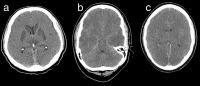

Prognose des neurologischen Outcomes nach Herz-Kreislaufstillstand: Macht Temperaturmanagement einen Unterschied? // Prognostication of Neurological Outcome after Cardiac Arrest: Does Hypothermia makes a Difference?